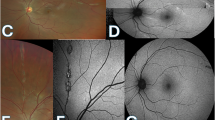

The study included 12 patients (24 eyes) with WNV-associated chorioretinitis. All the patients underwent a complete ophthalmic evaluation, including dilated fundus examination, fundus photography, fluorescein angiography, and indocyanine green angiography. Characteristics of linear streaks, particularly their relationship to the course of retinal and choroidal vessels, and pattern of retinal nerve fibres, were analysed.

All patients had bilateral multifocal chorioretinitis with linear clustering of chorioretinal lesions associated with a variable number of scattered lesions. Linear streaks, variable in number and length, originated from the optic disc or its vicinity in most cases. Their course in all cases appeared to closely follow the course of retinal nerve fibres, rather than that of retinal or choroidal vessels.

Results of our study show that the linear pattern of WNV-associated chorioretinitis is related to retinal nerve fibres organization, suggesting a contiguous spread of WNV virus from central nerve system via the optic nerve fibres to the outer retina, retinal pigment epithelium, and choroid.